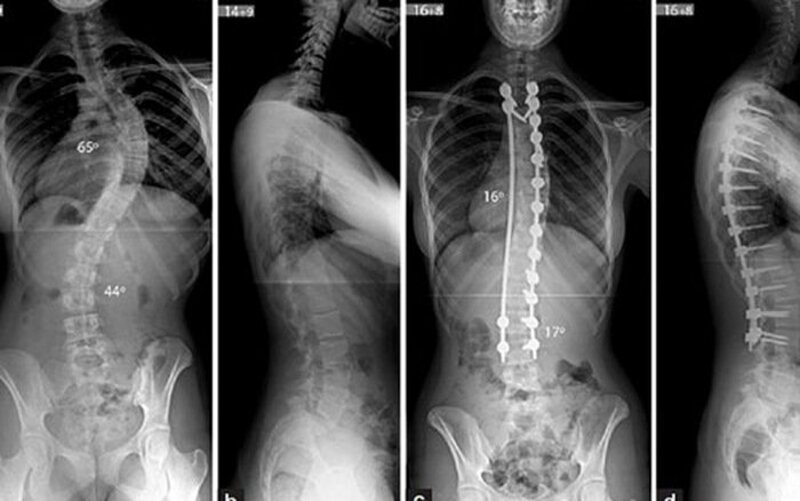

Vẹo cột sống

Bạn nên chụp x quang lưng khi bị chấn thương hoặc có dấu hiệu bất thường ở vùng cột sống. Chụp x quang cột sống được thực hiện để kiểm tra độ cong của cột sống hoặc các khuyết tật ở cột sống. Tia X được sử dụng trong chụp x quang là một dạng bức xạ tương tự như sóng vô tuyến hoặc chùm tia sáng của đèn pin có thể xuyên qua nhiều vật thể và tạo ra hình ảnh vật thể bằng cách chiếu một máy dò và sau đó gửi hình ảnh đến máy tính. Do đó, trên hình ảnh x quang, các mô dày đặc trong cơ thể sẽ có màu trắng, trong khi các mô ít dày đặc hơn sẽ có màu xám.